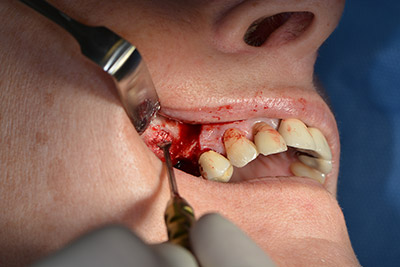

The next step was the sinus floor elevation with simultaneous implantation. The Implantmed also had a presetting at the first position for the buccal fenestration of the maxillary sinus wall.

The fenestration was prepared at 35,000 rpm and then the nasal mucosa were prepared in the cranial direction (Fig. 13 to 14).

The implant was then placed and the bone built up. In this case, because of the size of the augmentation region, autologous bone chips, harvested with an osseous trap as drilling chips from implantation 16 and fenestration 14, were mixed with bone replacement material.

An absorbable membrane was used as the barrier in the buccal direction and covered the augmentation. Finally, saliva-proof sutures were placed (Fig. 15 to 19).